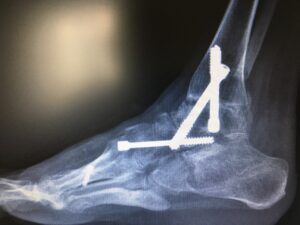

Skomplikowana operacja odtwórcza. Trzeba podczas operacji wyobrazić sobie nową konstrukcję stopy, żeby wytrzymała obciążenie, była bardziej funkcjonalna – no i piękniejsza.

Wykonałem potrójną artrodezę oraz usztywnienie stawu skokowego górnego w skorygowanym ustawieniu.